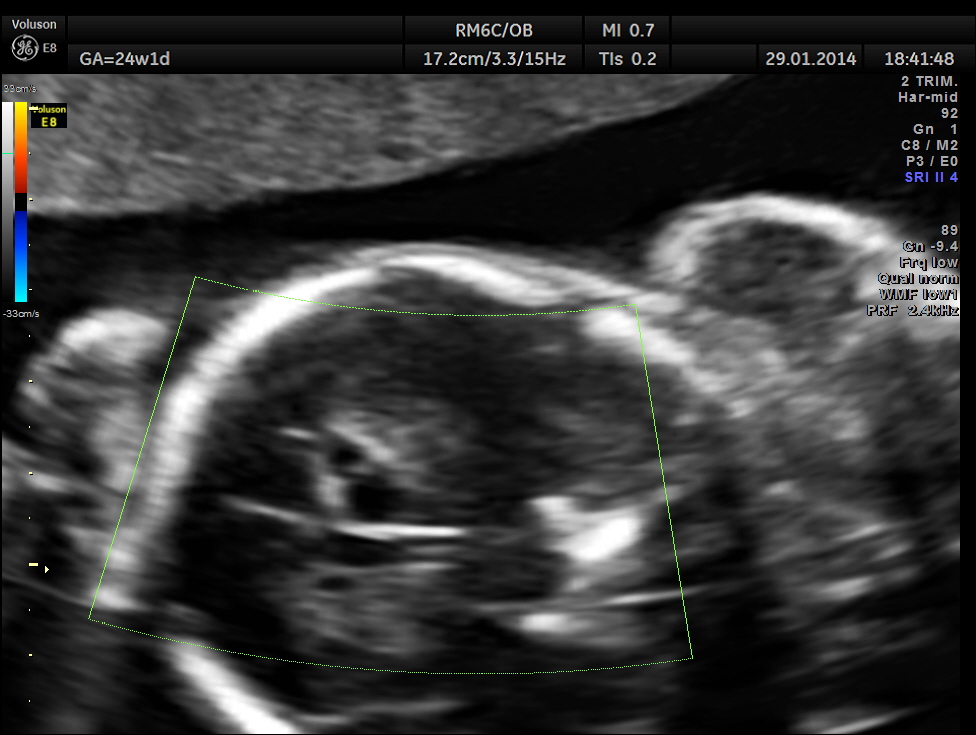

This was a 32-year-old lady – primi gravida . She was referred for an anomaly scan around 24 weeks gestation.Her earlier scan done in the first trimester elsewhere was reported as normal.

The following images were obtained. Unilateral choroid plexus cyst was seen .

Images of the other organs are given below.